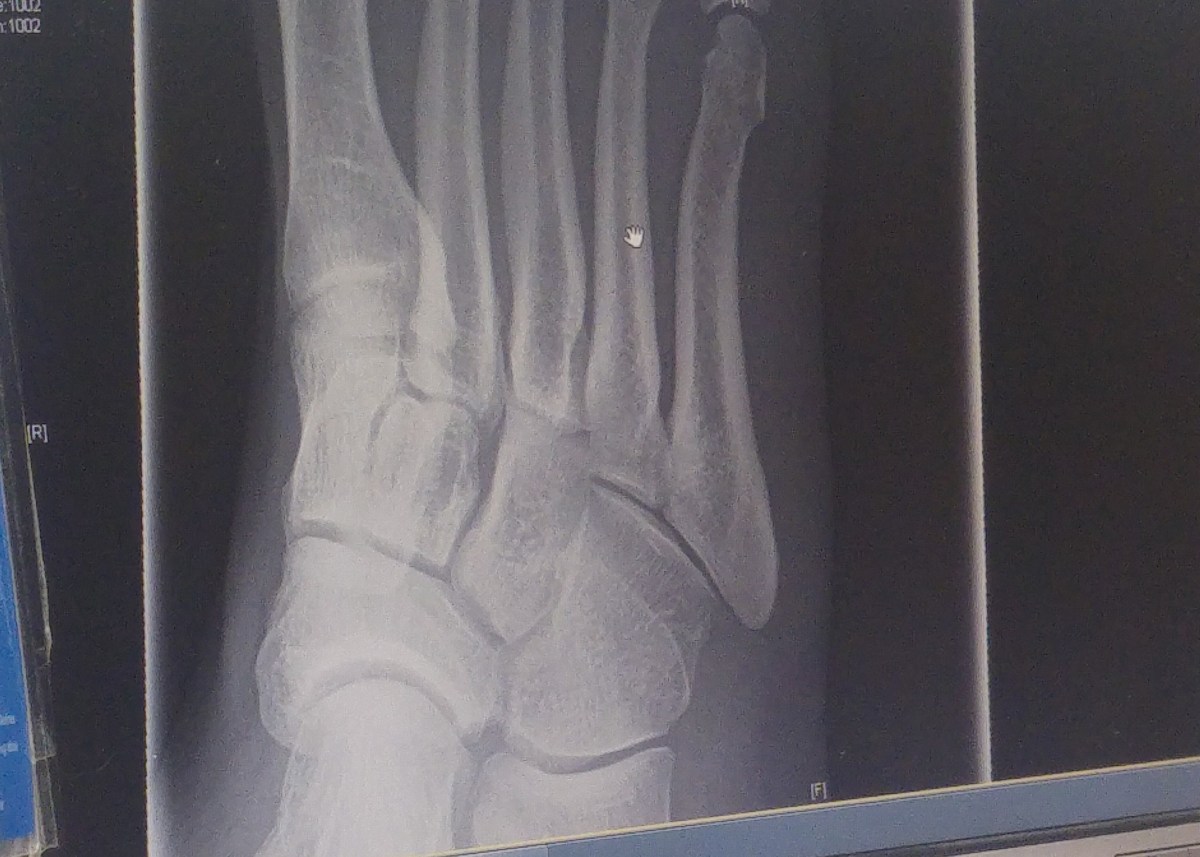

Anyway, I got an x-ray and they didn’t think it was a fracture. It could be but the type of fracture might not show up this early. Given an examination though they reckoned it was not a break.